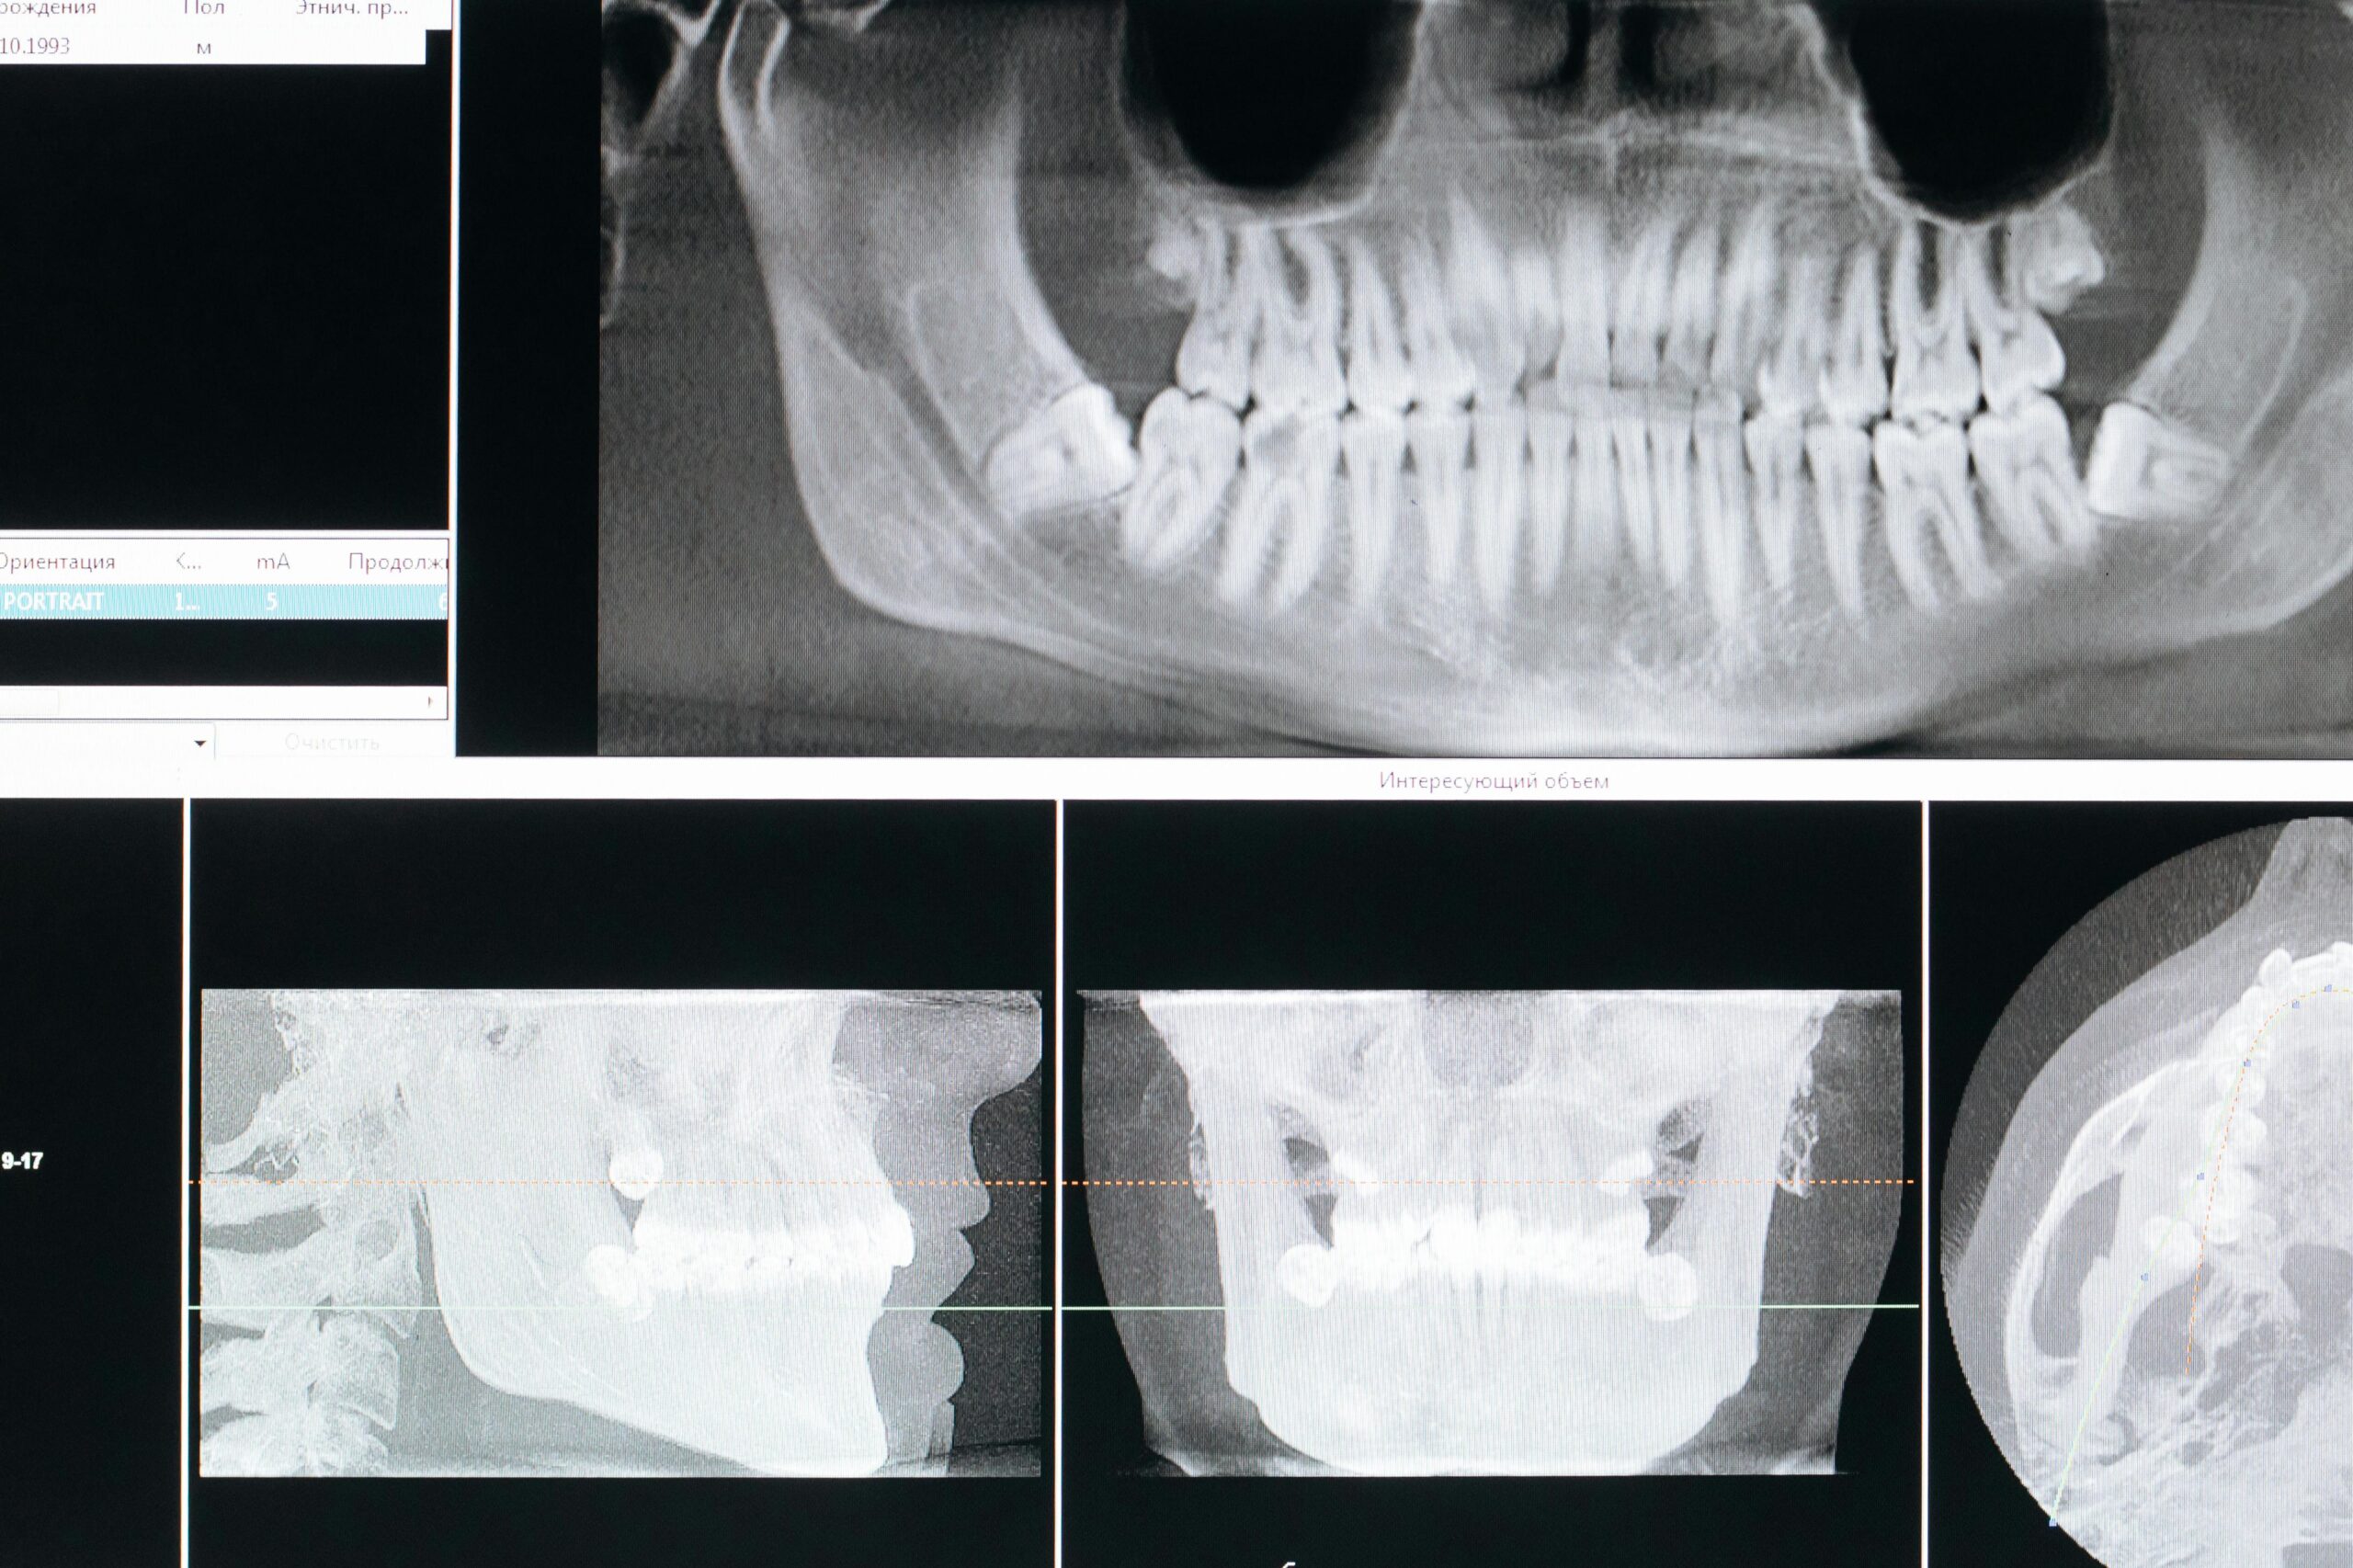

Prevent Bone Loss

Dental implants force your bone to heal around them, preventing any further bone loss